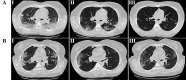

Results: A total of 24 patients in the intervention group and 20 patients in the control group completed the treatment. Compared with the control group, the clinical symptoms such as cough, dyspnea, and fatigue, as well as the level of CRP and the pulmonary involvement in the intervention group had significantly improved (p <0.05). The mean time of hospital discharge of patients and return to baseline health was significantly shorter in the intervention group compared to the control group (p <0.05). No deaths and adverse events were observed in both groups.